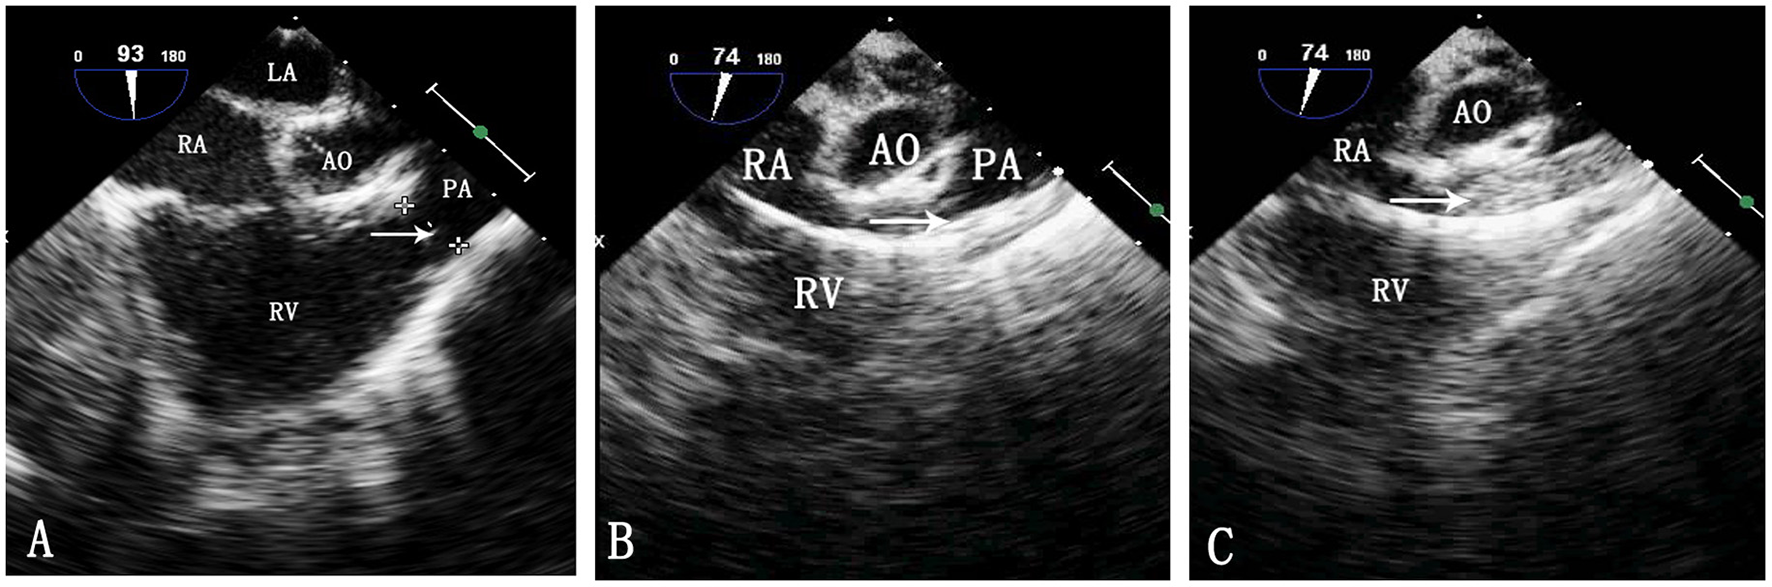

Figure 1

TEE image during pulmonary balloon valvuloplasty. LA, left atrium; RA, right atrium; Ao, aorta; RV, right ventricle; PA, pulmonary artery. (A) Measurement of the pulmonary valve annulus by TEE. The arrow shows the pulmonary valve annulus. (B) Passing of the catheter through the pulmonary artery. The arrow indicates the catheter. (C) Inflation of the balloon. The arrow indicates the balloon.